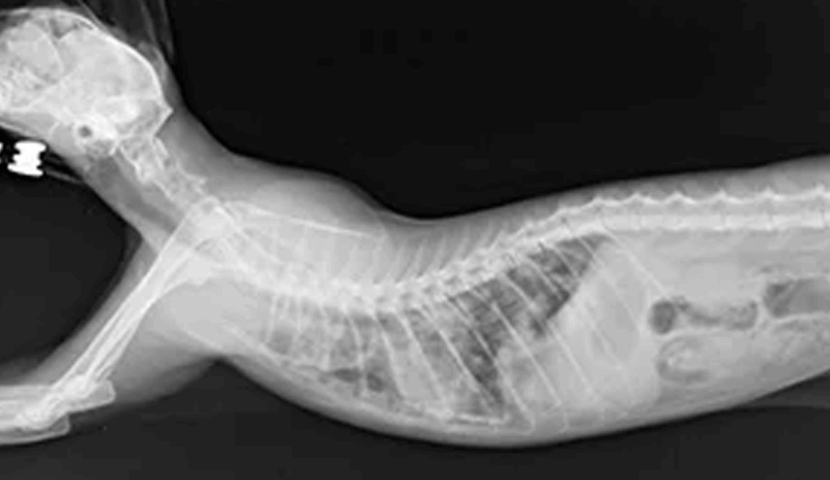

雑種猫 2歳

血液検査で白血球数の上昇、レントゲン検査で肺野全体の不透過性亢進が見られ、肺炎と診断。

| 若い猫に多い疾患です。来院時は呼吸困難の状態だったため、数日間ICUの酸素室で集中治療を行いました。細菌感染が原因であることも多く、点滴と積極的な抗生剤治療で改善しました。現在は元気に日常生活を送っています。 |